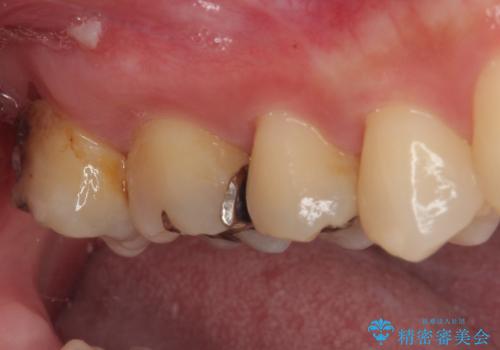

- 元々むし歯があったものの、処置が困難とのことでしたが、矯正治療を終えたので処置をしたいとのことで来院された患者様です。

左右ともに最後臼歯が頬側に顕著に突出しており、むし歯になってしまったことが想像されました。

矯正治療により処置が可能な位置に歯が移動したため、オールセラミッククラウンにて補綴治療を行うこととしました。

歯列が移動したとはいえ、左右ともに後方傾斜しており、むし歯の除去、形成(形を整える)、型取りの全てが非常に困難な処置となりました。

セラミッククラウンの適合はレントゲン写真からも分かる通り、境界がぴったりと合った、高適合のものとなりました。